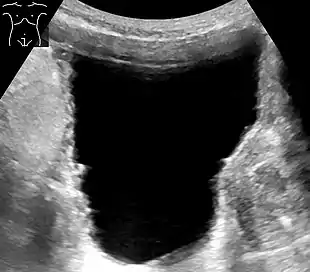

Ultrasonography showing a trabeculated wall, seen as small irregularities mainly at left (superior part). This is strongly associated with urinary retention.[7]

Analysis of urine flow may aid in establishing the type of micturition (urination) abnormality. Common findings, determined by ultrasound of the bladder, include a slow rate of flow, intermittent flow, and a large amount of urine retained in the bladder after urination. A normal test result should be 20-25 mL/s peak flow rate. A post-void residual urine greater than 50 ml is a significant amount of urine and increases the potential for recurring urinary tract infections. In adults older than 60 years, 50-100 ml of residual urine may remain after each voiding because of the decreased contractility of the detrusor muscle.[6] In chronic retention, ultrasound of the bladder may show massive increase in bladder capacity (normal capacity is 400-600 ml).